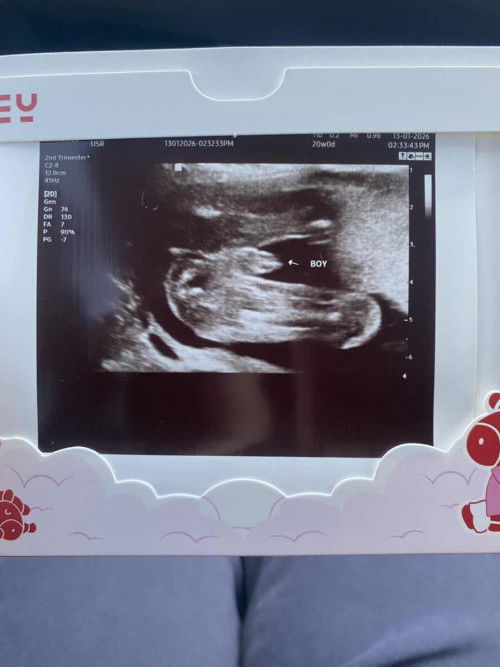

Baby boy or girl

Doctor cakap boy, tapi betul ka boy? 🥲

kenapa ya rata" org mengandung sllu tnya gender kalau dah terang" sana tulis boy 🤦🏻♀️🤦🏻♀️ apaa laa

Sebab kadang boleh jadi salah. Ada yang scan boy, tapi keluar girl. Sebab boleh jadi tu tali pusat. Dan ada yang scan girl tapi keluar boy. Sebab gender baby ni kadang by scan saja boleh salah. Manusia kan, kadang buat silap sebab kita tak dapat 100% pastikan itu boy/girl sampai lah dia bebetul keluar 🙂

Inshallah betul. Boleh repeat scan on 24 weeks kalau tak yakin

𝑛𝑖 𝑛𝑚𝑝𝑘 𝑚𝑐𝑚 𝑏𝑜𝑦 𝑗𝑒

𝑠𝑏𝑏 𝑛𝑚𝑝𝑘 𝑚𝑢𝑛𝑐𝑢𝑛𝑔 𝑏𝑖𝑟𝑑 𝑡𝑢 🤭

Betul boy. Terang2 nampak telurnya.😂

brpa minggu ye boleh tau jantina?

Ni 20week sis